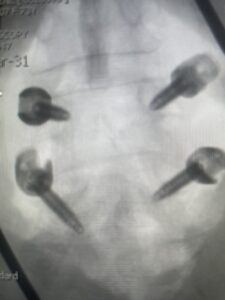

Fig 3: Lateral and AP fluoroscopic images demonstrating placement of pedicle screws for L4-5 fusion for spondylolisthesis.